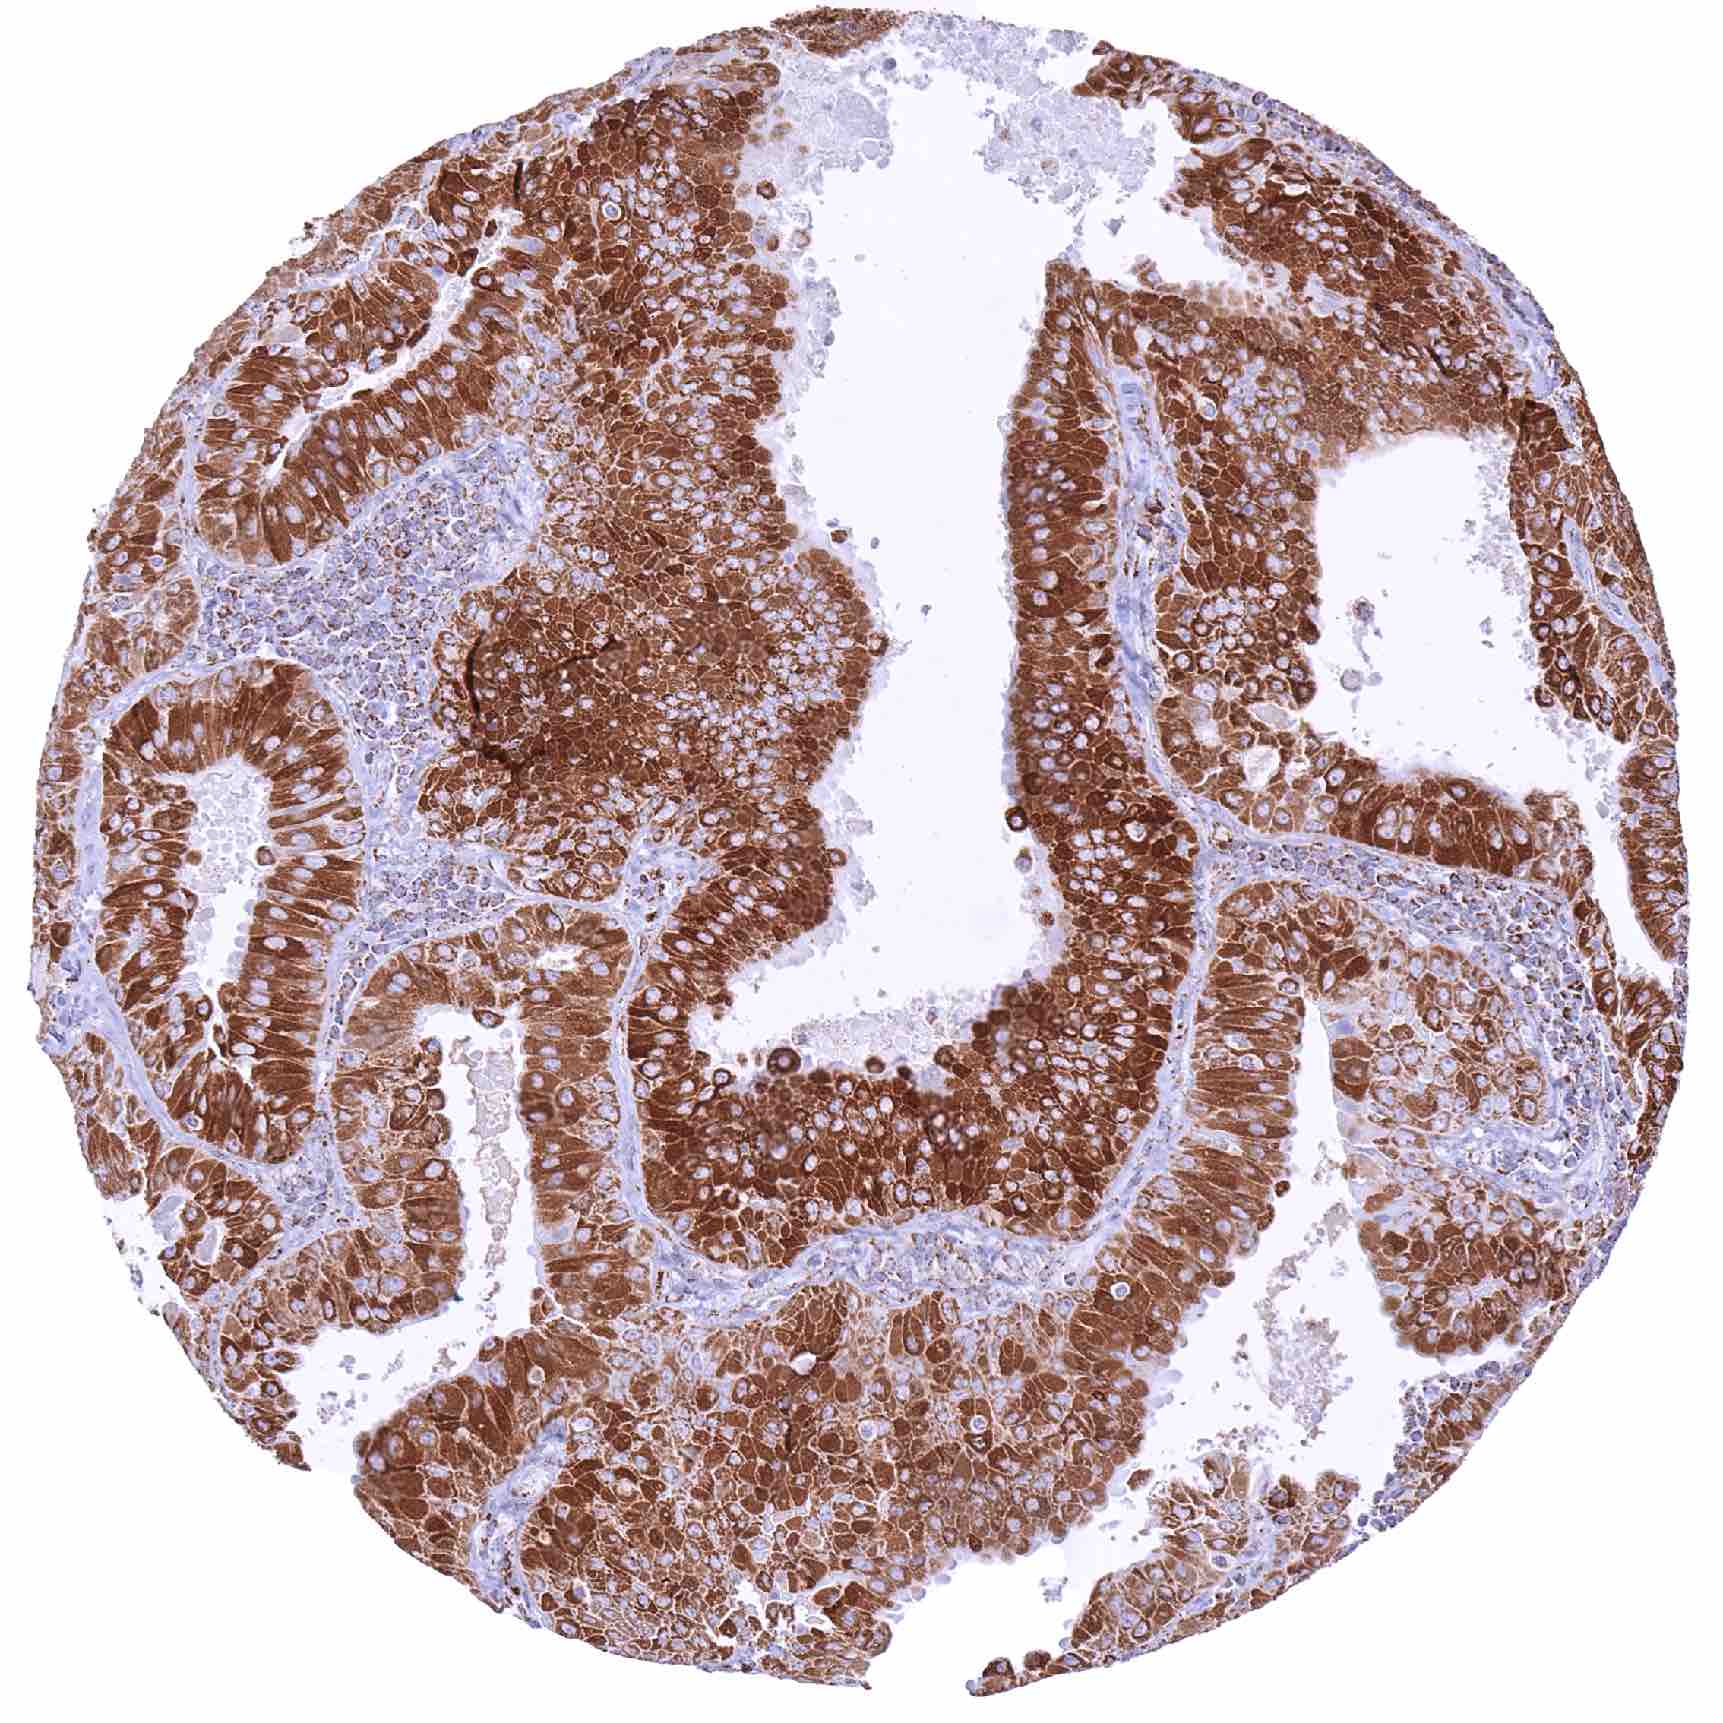

Prostate – Adenocarcinoma (Gleason 5+5=10) with only a faint granular cytoplasmic SDHA staining of tumor cells. The SDHA staining is markedly more intense in entrapped normal glands